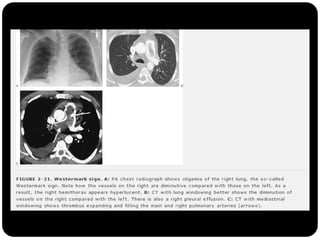

Sinal deWestermark

O que foivisto até agora?  Cistos (LAM, Histiocistose de Langerhans, PIL)  Bolhas  Cavidades (diss. hemat. de infecção, neoplasia,TB, gran. Wegerner)  Enfisema (centrolobular)  Padrões e sinais torácicos Sinal deWestermark Sinal da corcova de Hampton Sinal de árvore em brotamento Perfusão em mosaico ( X vidro fosco) Faveolamento - fibrose